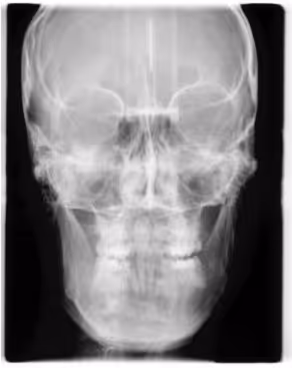

La téléradiographie céphalométrique est un examen d’imagerie médicale permettant une analyse détaillée du crâne, des mâchoires et des tissus mous du visage.

Cet outil diagnostique est particulièrement utilisé en orthodontie pour l’évaluation des structures osseuses et dentaires, facilitant ainsi l’élaboration des plans de traitement.

L’intérêt principal de la téléradiographie réside dans sa capacité à fournir une image en taille réelle et sans déformation des structures cranio-faciales. Elle permet d’évaluer l’inclinaison des dents, la position des mâchoires et la relation entre les bases osseuses, ainsi que l’harmonie des tissus mous tels que le front, le nez, les lèvres, le menton.